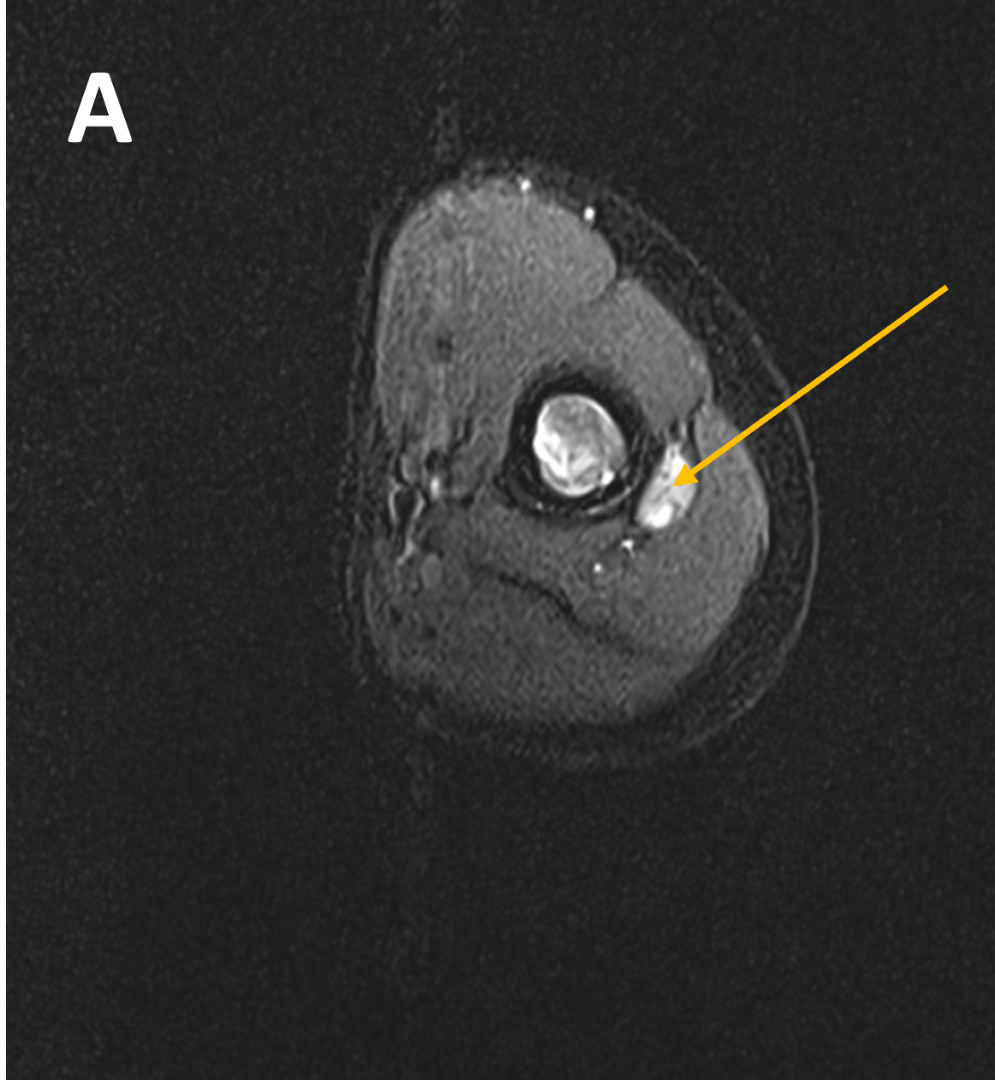

- (A,B) : MR LEFT FOREARM

- B 1 : Tract of previous intramedullary nail seen in shaft of humerus, along with mild diffuse cortical thickening.

- B 2 : Volume loss with fatty atrophy of brachioradialis, supinator, extensor carpi radialis longus and brevis muscles ,due to chronic denervation changes.